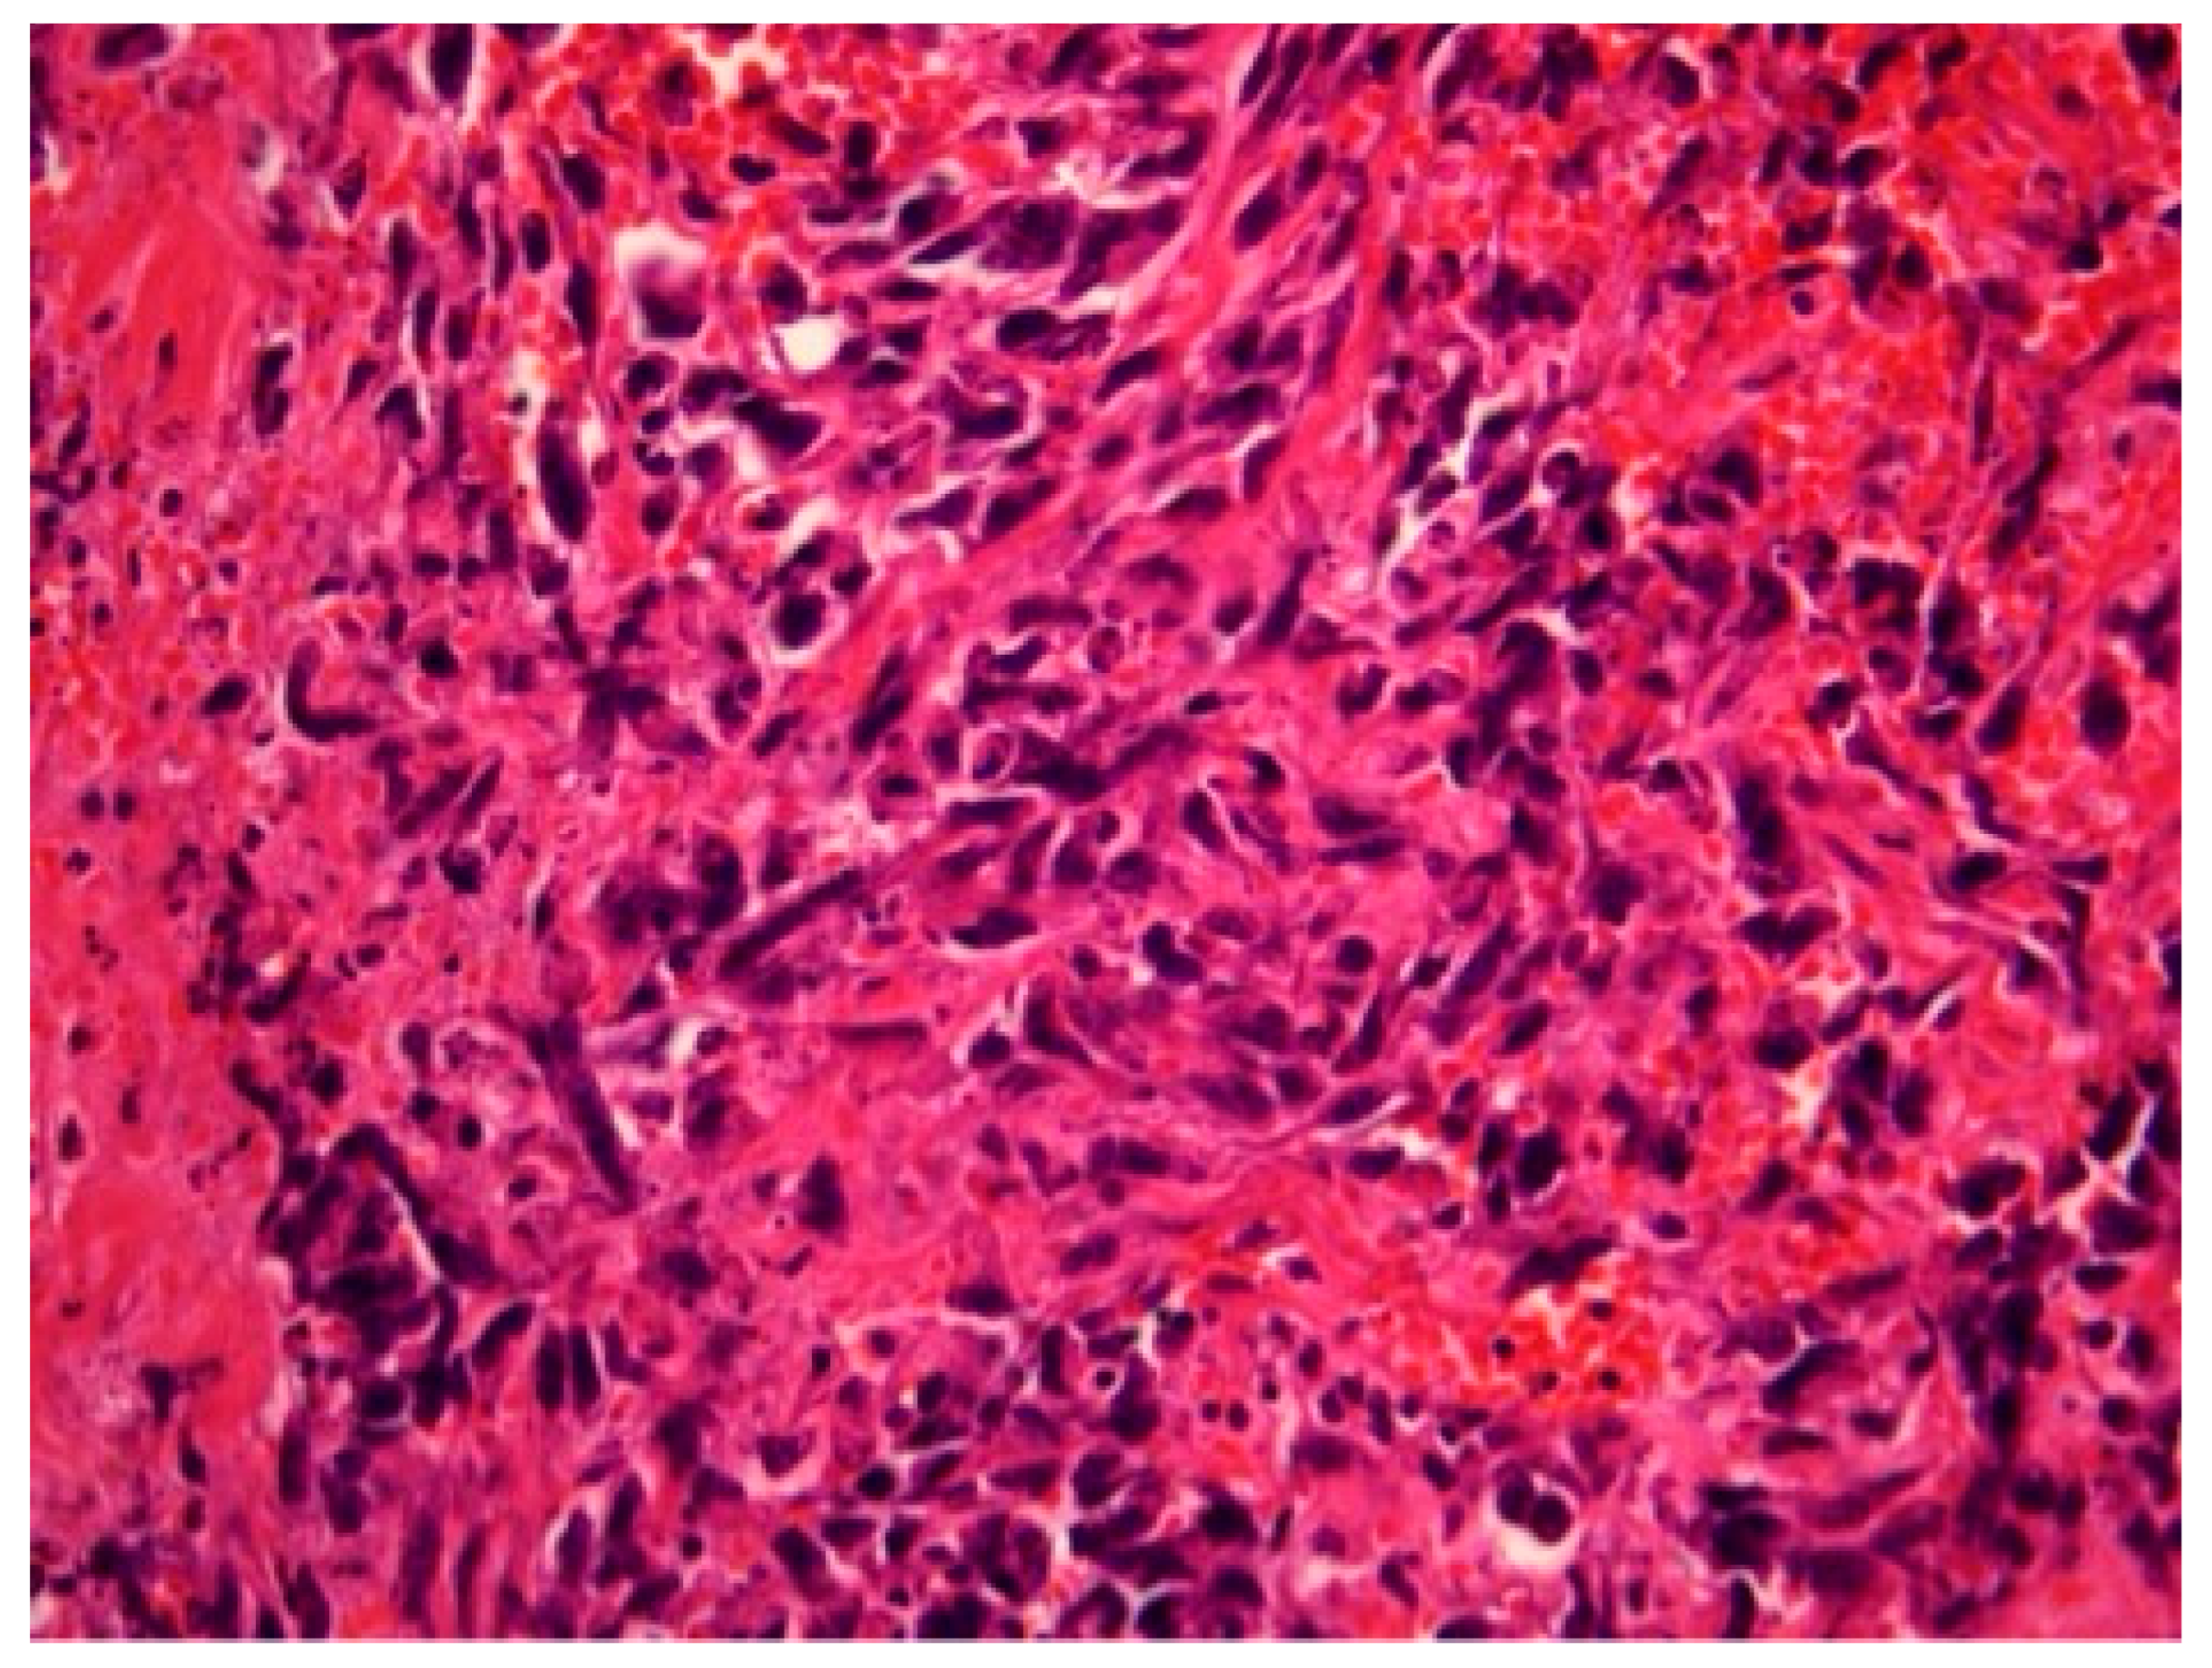

Figure 1, Figure 2 and Figure 3 show the RIBAS clinical presentation and pathology results. Detailed RIBAS clinical presentations and treatment strategies are summarized in Table 2 and Table 3. No patient had active BC at the time of RIBAS diagnosis, nor did any patient develop recurrent BC during the RIBAS follow-up. Median age at RIBAS diagnosis was 64 (range: 36–68) years, while the estimated median time from BC RT to RIBAS diagnosis was 64 (95% CI > 57) months. Mean tumor size at RIBAS diagnosis was 55 (SD 32.78) mm. All nine patients had localized disease and underwent total mastectomy with curative intent. Four patients needed pectoral defect reconstruction. A total of four patients received adjuvant chemotherapy, three of whom received doxorubicin as monotherapy, while the remaining patient had doxorubicin and cyclophosphamide combination (AC protocol). The patients were followed up for a median of 30 (range: 7–40) months after the initial RIBAS operation. Local recurrence was observed in seven patients, five of whom had surgery with curative intent. Three patients developed distant metastases during follow-up.

Figure 2. Radiation-induced breast angiosarcoma—microscopic analysis, HE staining, 40 × 1.